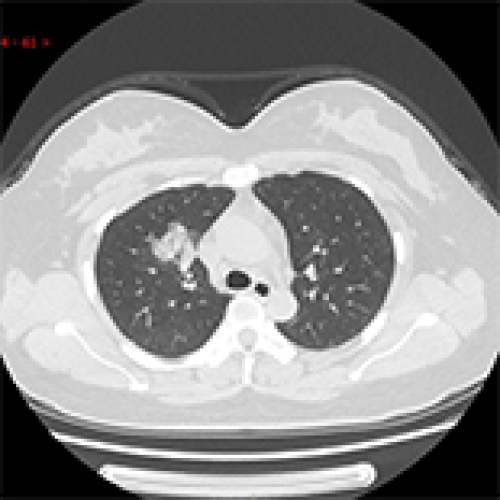

14 Nov 2021 : Clinical Research

Clinical Features and Temporal Lung Radiographic Changes in 25 Patients Recovering from COVID-19 Pneumonia: A Retrospective Case-Control Study

Chao Hu, Jian Ping Zeng, Ke Peng, Hong Xia, Huan Ming Zhang, Zhi Zhong, Ming Yan Jiang

DOI: 10.12659/MSM.933381

Med Sci Monit 2021; 27:e933381

3,640 973 0

3640 973 0